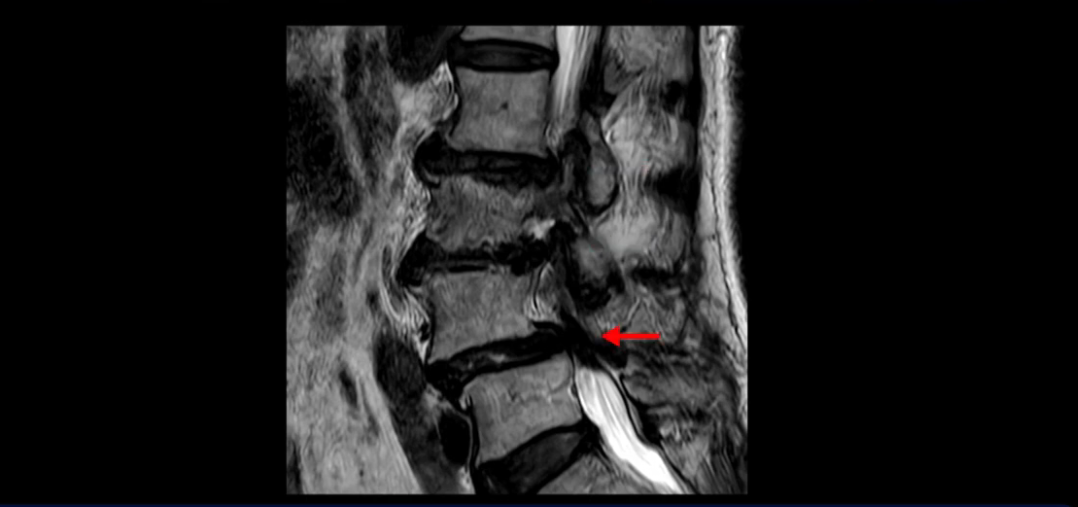

먼저 이분 MRI를 보고 자세히 설명해 드린 후 어떻게 허리 여러 마디에서 협착과 전방전위로 신경이 심하게 눌려 보이는 환자가 수술 없이 좋아질 수 있는지, 또 치료는 어떻게 하는지 설명해 드리겠습니다.

이분 MRI 보시면 허리 3마디의 퇴행이 매우 심합니다.

4번 5번에는 뼈가 밀려 나간 전방전위증도 있고,

또 척추관협착도 매우 심합니다.

척추관이 심하게 좁아져 있습니다.

이렇게 여러 마디가 안 좋고 뼈도 밀려 나가 있으니까 나사박는 수술해야 하는데, 대학병원에서도 수술을 한 번에 못 하고 두 번에 나눠서 해야 한다고 들으셨습니다. 왼쪽으로 신경가지가 빠져나가는 추간공도 많이 좁아져 있습니다.

이렇게 신경 구멍들이 좁아져 있고 신경이 눌리니까 엉덩이와 다리가 너무 저리고 아파서 아예 일어서질 못하니까 휠체어를 타고 병원에 내원하셨는데요. 그럼 어떻게 이분처럼 신경이 눌려있는 환자분들을 수술 없이 치료해서 잘 걷게 만들고 엉덩이와 다리가 저리고 아픈 증상이 사라지게 할까요? 지금부터 설명해 드립니다.